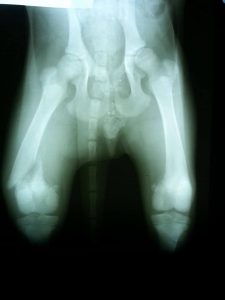

Op de foto was de breuk duidelijk te zien, linker achterpoot en op een plek waar opereren niet mogelijk is.